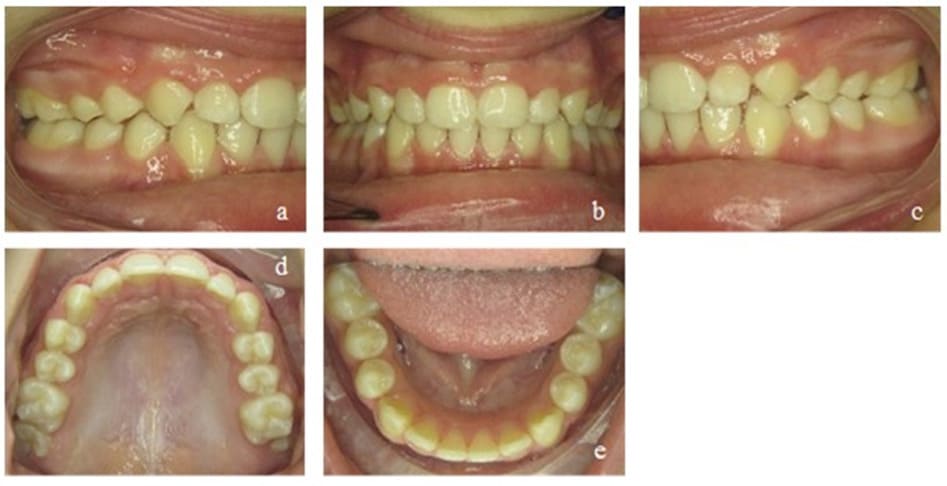

Figure 6: Case 1. Interims findings after 6 months of treatment. Frontal view of the occlusion (b), occlusion right (a) and left (c). Upper (d) and lower arch (e).

During the next treatment phase (another six months), the patient continued wearing the appliance and performing selected exercises as advised. The dental situation continued to improve, showing a physiological overjet of 2 mm with occlusal contact of all incisors and no crowding. However, the torque of the maxillary front teeth had still to be corrected (Figure 7). The strength of the tongue and its resting position on the palate also improved.

Figure 7: Case 1. Second interims findings after 12 months of treatment. Frontal view of the occlusion (b), occlusion right (a) and left (c). Upper (d) and lower arch (e).